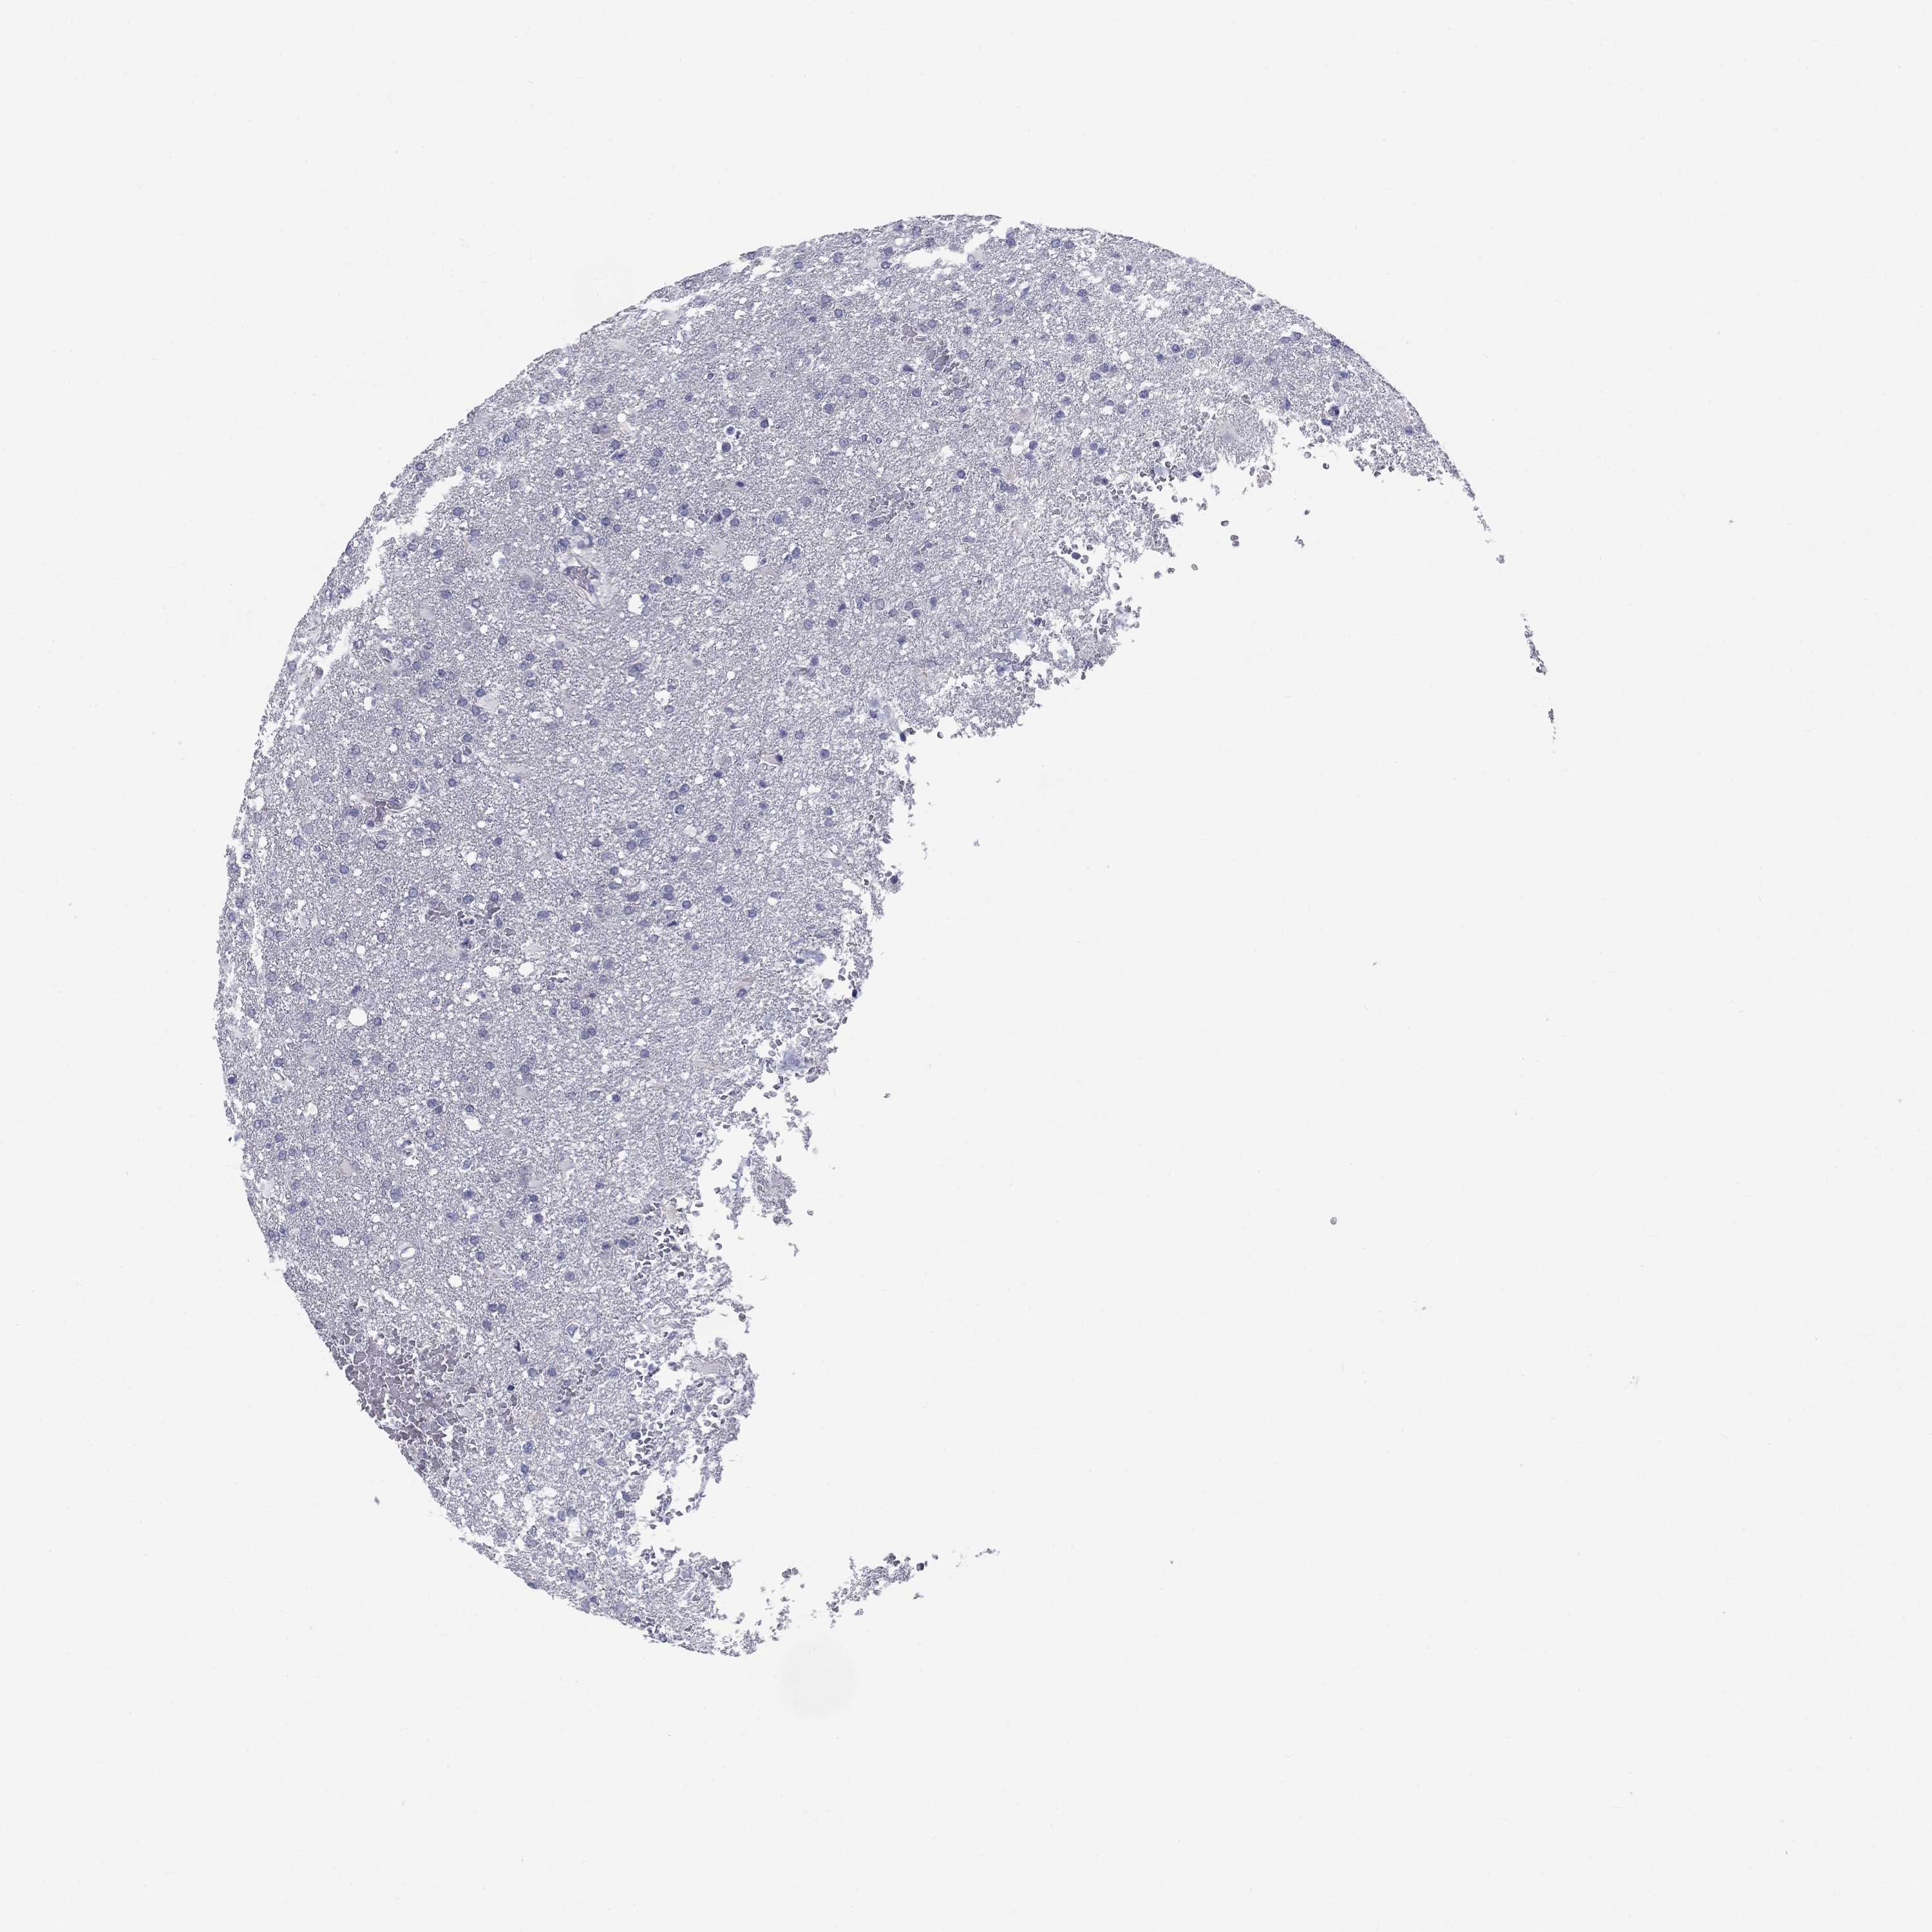

GLIOMA - Protein expressioni

A mouse-over function shows sample information and annotation data. Click on an image to view it in a full screen mode. Samples can be filtered based on level of antibody staining by selecting one or several of the following categories: high, medium, low and not detected. The assay and annotation is described here.

Note that samples used for immunohistochemistry by the Human Protein Atlas do not correspond to samples in the TCGA dataset.

Antibody stainingi

Antibody staining in the annotated cell types in the current human tissue is reported as not detected, low, medium, or high, based on conventional immunohistochemistry profiling in selected tissues. This score is based on the combination of the staining intensity and fraction of stained cells.

Each image is clickable and will lead to virtual microscopy that enables deeper exploration of all samples and also displays staining intensity scores, fraction scores and subcellular localization as well as patient and tissue information for each sample.

Antibody HPA068138

Antibody HPA071902

Staining

High

Medium

Low

Not detected

Intensity

Strong

Moderate

Weak

Negative

Quantity

>75%

75%-25%

<25%

None

Location

Nuclear

Cytoplasmic/membranous

Cytoplasmic/membranous,nuclear

Glioma, malignant, Low grade

Glioma, malignant, High grade

Glioma, malignant, NOS